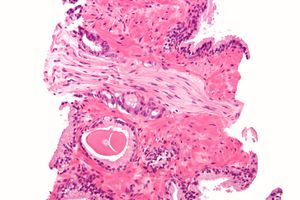

A diagnosis of prostate cancer requires a biopsy of the prostate. Prostate biopsies are typically taken by a needle passing through the rectum or perineum, guided by transrectal ultrasound imaging, magnetic resonance imaging (MRI), or a combination of the two.[10][8] Ten to twelve samples are taken from several regions of the prostate to improve the chances of finding any tumors.[8] Biopsies are examined under a microscope by a pathologist, who determines the type and extent of cancerous cells present. Cancers are first classified based on their appearance under a microscope. Over 95% of prostate cancers are classified as adenocarcinomas (resembling gland tissue), with the rest largely squamous-cell carcinoma (resembling squamous cells, a type of epithelial cell) and transitional cell carcinoma (resembling transitional cells).[11]

Micrograph showing a prostate cancer (conventional adenocarcinoma) with perineural invasion. H&E stain.

Next tumor samples are graded based on how much the tumor tissue differs from normal prostate tissue; the more different the tumor appears, the faster the tumor is likely to grow. The Gleason grading system is commonly used, where the pathologist assigns a number from 1 (most similar to healthy prostate tissue) to 5 (least similar) for the most common pattern observed under the microscope, then does the same for the second-most common pattern. The sum of these two numbers is the Gleason score.[11] The total scores of 2 through 5 are no longer commonly used in practice, making the lowest score 6, and the highest score 10. Scores are commonly grouped into Gleason grade groups: a score of 6 or lower is Gleason grade group 1; a score of 7 with the first number (from the most common pattern) 3 and the second number 4 is grade group 2; the reverse – first number 4, second number 3 – is grade group 3; a score of 8 is grade group 4; a score of 9 or 10 is grade group 5.[11] Higher Gleason scores and higher grade groups represent cancer cases likely to be more aggressive with worse prognosis.[11]